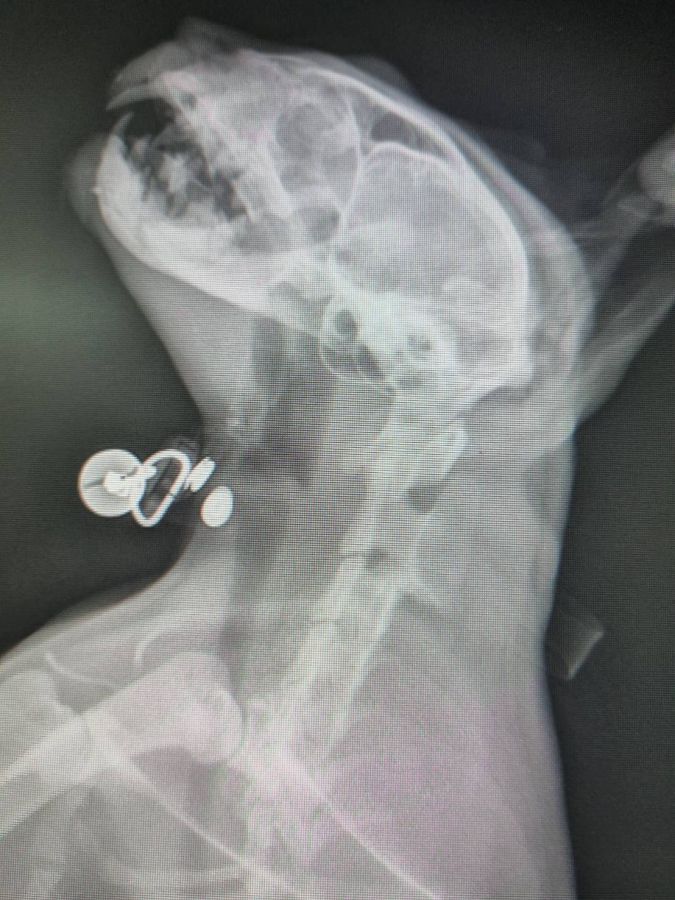

Raising funds to help a cat hit by a car and broken jaw

สวัสดีค่ะเราปิงเจ้าของแมวค่ะเงินบริจาคที่เราเปิดรับนี้เพื่อนำมารักษาแมวเราค่ะคือแมวเราโดนรถชนค่ะช่วงประมาณตี 4 เราลงมาจากบ้านแล้วยายเราเห็นค่ะว่าน้องนอนอยู่เราเลยพาไปรพในตอนที่ฟ้าสว่างกันคุณหมอบอกว่าน้องกรามล่างหักค่ะซึ่งค่าใช้จ่ายคือหมื่นกว่าบาทในเบื้องต้นแต่ทางรพไม่มีหมอกระดูกที่ผ่าตัดได้เลยต้องหาที่อื่นโดยที่เรายังไม่มีใบค่ารักษาที่แน่นอนแต่ราคาอยู่ในเกณฑ์ประมาณที่เรารับบริจาคค่ะเราอยากให้น้องหายเลยอยากเปิดรับบริจาคให้เร็วที่สุดเพราะถ้าเรายังฝากน้องไว้ค่าใช้จ่ายก็จะสูงมากกว่าเดิมทางบ้านเราไม่มีเงินพอสำหรับการรักษามันสำคัญจริงๆเพราะเป็นแมวที่เรารักถ้าเรารักษาน้องหายแล้วเราจะพาน้องมาแนะนำแต่ในตอนนี้แค่รูปน้องหมอยังไม่ให้เราถ่ายเลยขอความกรุณาด้วยนะคะ